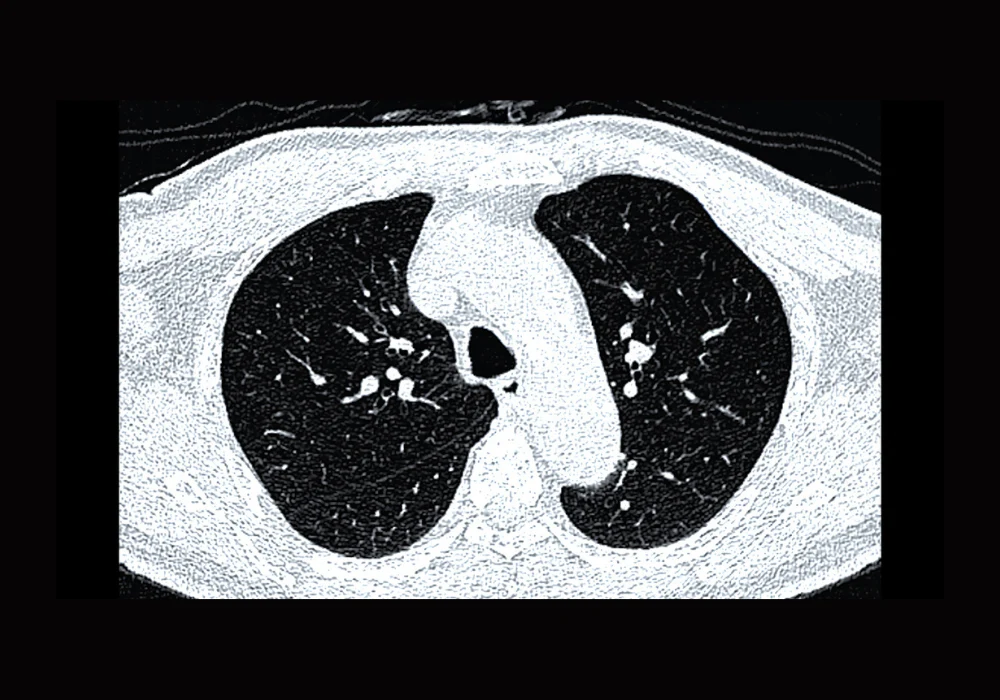

Three hundred consecutive participants from the NELCIN-B3 programme in Tianjin were included after excluding cases with missing or poor-quality reconstructions. The mean age was 61.2 years, 53.0% were women, and 35.6% were current or former smokers with a mean 22.7 pack-years. All scans used a 128-detector row CT in a low-dose protocol. Reconstructions comprised a medium-soft kernel at 1 mm (D45f/1 mm), a sharp kernel at 1 mm (B80f/1 mm), and a soft kernel at 2 mm (B30f/2 mm). To isolate thickness effects under the same kernel, a 2-mm series was also created from D45f data by software reformation.

AI analysis used a commercial deep learning system that detects, segments and classifies nodules. The pipeline had been trained on a public dataset, generated candidates with convolutional networks, and reduced false positives with a second stage. Segmentation combined intensity thresholds with a deformable model. Classification produced four types: noncalcified solid, part-solid, nonsolid or calcified. Outputs included nodule location and size, including solid components.

Radiologist agreement on the presence of a risk-dominant nodule was almost perfect. AI agreement with the reference depended strongly on kernel selection. With the medium-soft kernel at 1 mm, agreement was moderate to substantial and scan-level sensitivity was clearly higher than with the sharp kernel at the same thickness. Specificity differences between these two 1-mm settings were small. When thickness and interval changed from 1.0/0.7 mm to 2.0/1.0 mm under the same medium-soft kernel, AI sensitivity and specificity were not meaningfully altered. Performance under the two 2-mm reconstructions showed no important advantage for either kernel in scan-level detection, reinforcing that the large shift came from kernel choice at thin slices rather than from the thickness change within the tested range.

For matched nodules, kernel selection had a marked effect on type classification. Agreement with the reference was high with the medium-soft kernel at 1 mm and fell sharply with the sharp kernel at 1 mm. At 2 mm, agreement remained higher with the medium-soft option than with the soft kernel. There was no meaningful difference between 1-mm and 2-mm series under the medium-soft kernel for type classification, which again points to kernel choice as the main driver within the tested thickness range.

Patterns of error differed by kernel. With the sharp kernel, noncalcified solid nodules were frequently mislabelled as calcified, shifting cases away from the risk-dominant category. With the soft 2-mm kernel, noncalcified solid nodules were more often misclassified as nonsolid. Both patterns matter because the presence and type of the risk-dominant nodule determine scan-level categorisation and follow-up. Using the same kernel as the radiologists improved alignment in type, likely because image texture and edges were represented in a similar way, which made the AI outputs more consistent with human assessment.